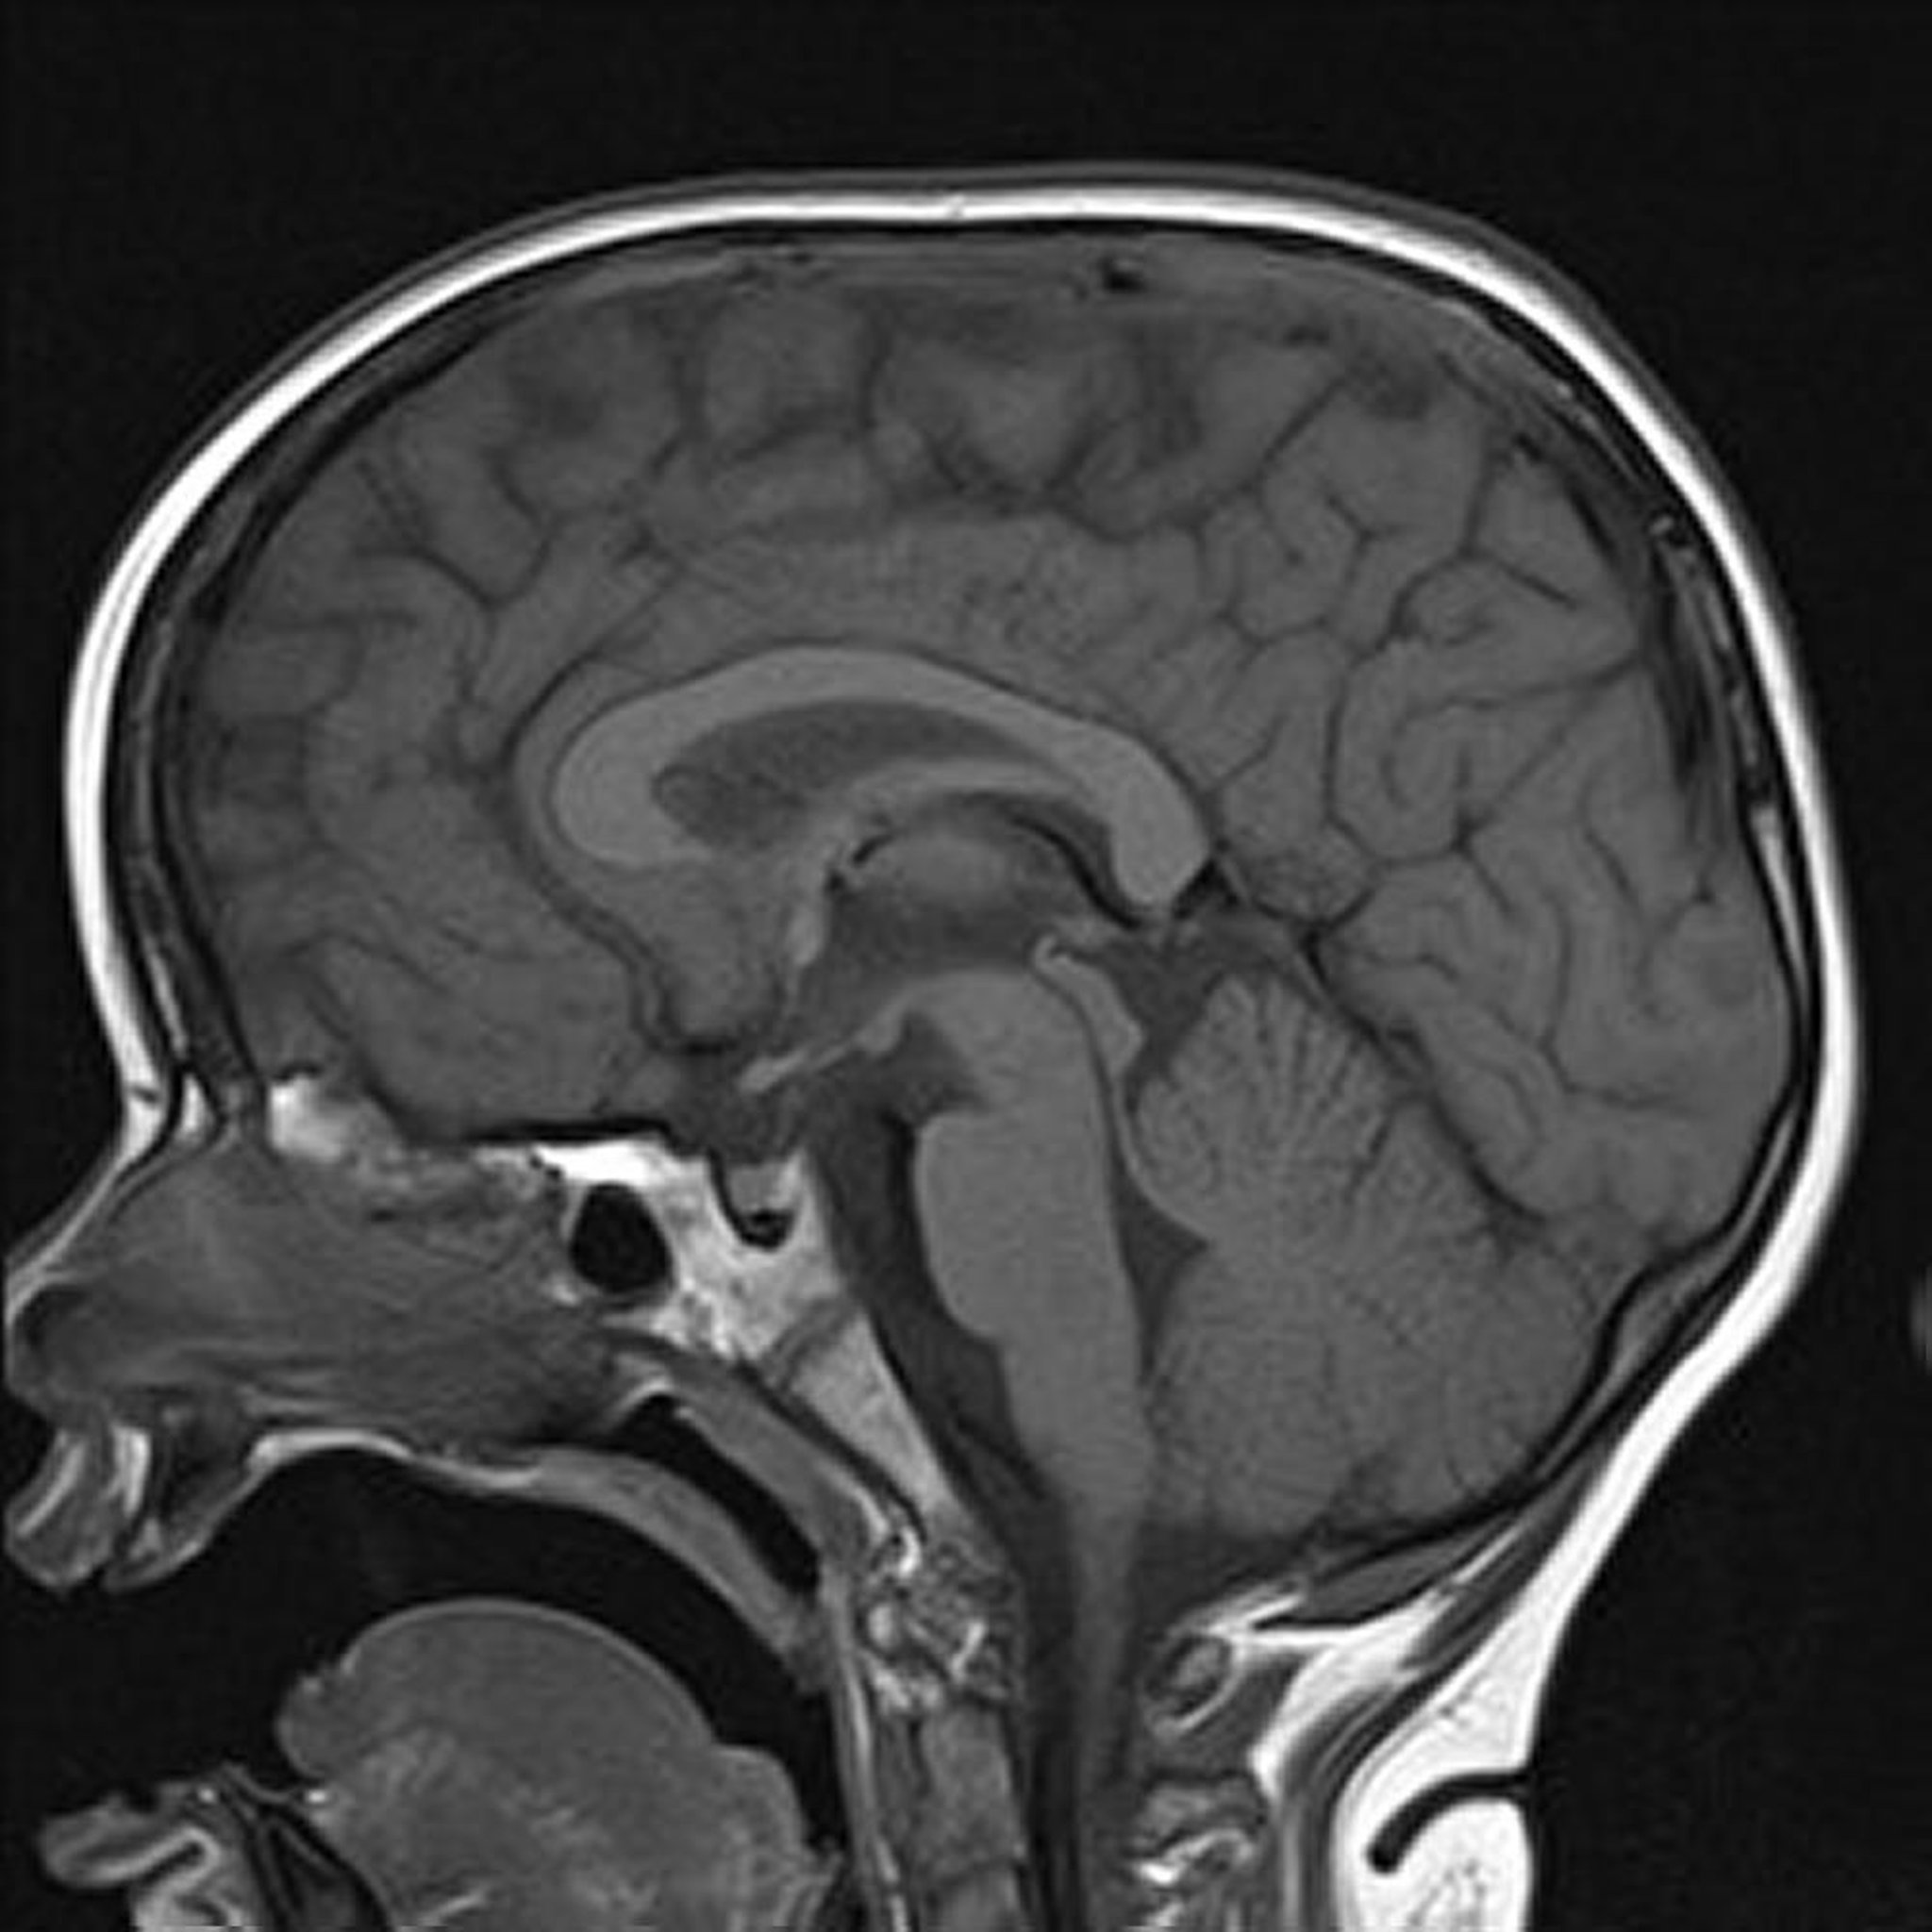

MRIのT1強調画像

この脳のT1強調矢状断像には,正常な正中線の構造が示されている。

Image courtesy of Hakan Ilaslan, MD.